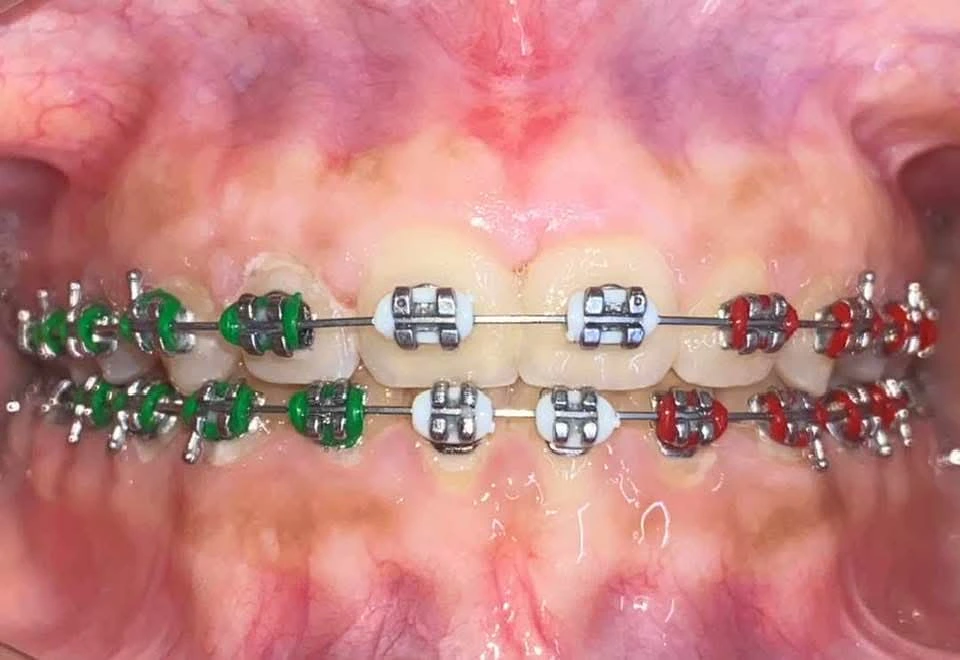

Corregimos la posición de los dientes y la mordida para lograr una sonrisa armónica y una función dental óptima. Este tratamiento, realizado por un especialista en Ortodoncia, transformara tu sonrisa y evitara problemas futuros en tu salud bucal.

Agenda tu citaOrtodoncia(Brackets)